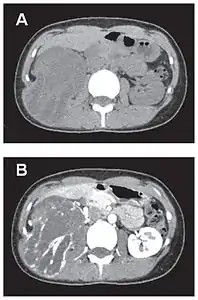

En tomodensitométrie[20],[31], quelle que soit la localisation, une tumeur fibreuse solitaire apparaît comme une masse tissulaire ovoïde ou lobulée, bien délimitée, refoulant les structures voisines sans les envahir. Elle se rehausse fortement après injection de produit de contraste. Les tumeurs de petite taille sont homogènes, mais les plus volumineuses présentent des plages hétérogènes de nécrose et d'hémorragie intra-tumorale. Il n'y a pas habituellement de calcifications et, lorsqu'elles sont présentes, elles sont de petite taille[31]. Les tumeurs malignes peuvent se présenter accompagnées de nodules pulmonaires métastatiques, et tendent à être plus volumineuses et plus hétérogènes[42].

Démarche diagnostique

Coupe tomodensitométrique montrant une tumeur intrathoracique où est plantée une aiguille à biopsie.

Ponction sous scanner d'une tumeur fibreuse solitaire pleurale.

Le diagnostic clinique est difficile en raison de l'absence de signes spécifiques, et nécessite la réalisation d'examens complémentaires[47]. Si le diagnostic peut être évoqué face à une imagerie typique, le diagnostic de certitude nécessite une approche anatomopathologique de la tumeur[5]. La ponction sous scanner aide ainsi à poser le diagnostic et à orienter le traitement[13]. En effet, les diagnostics différentiels sont multiples et dépendent de la localisation de la tumeur[41]. Le plus fréquent est la fibromatose, mais toutes les tumeurs tissulaires sont concernées, en particulier l'histiocytofibrome, les sarcomes, et les tumeurs germinales[17],[48].